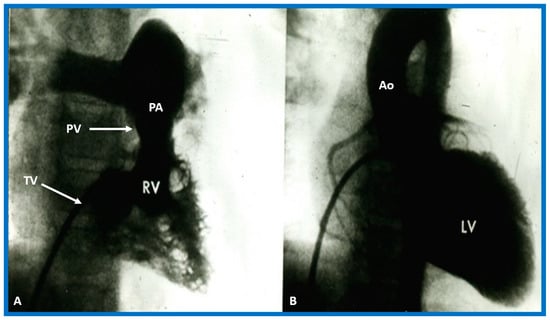

In theory, patients with cardiac malposition may have one (single) or two ventricles. The distinction between one and two ventricles is feasible by echocardiography (Figure 30) and angiography (Figure 31 and Figure 32).

Figure 31. Selected angiographic images demonstrating characteristic features of the right (A) and left (B) ventricles. The right ventricle (RV) exhibits coarse trabeculations (A), while the left ventricle (LV) shows smooth or fine trabeculations (B). In addition, the RV exhibits a triangular shape, whereas the LV is a foot-shaped structure. The tricuspid (TV) and pulmonary (PV) valves (arrows in (A)) are separated by a muscular structure, crista supraventricularis. Aorta (Ao) and pulmonary artery (PA) are labeled. Modified from reference [3].

Ventricular Trabeculations and Shape

The morphologic LV is a smooth-walled structure with fine trabeculations and a foot-shaped appearance, whereas the morphologic RV has coarse trabeculations and a triangular shape. These features are demonstrated by echocardiographic (Figure 34) and angiographic (Figure 31, Figure 35 and Figure 36) studies. It should be noted that the characteristic trabecular pattern of the ventricles is seen irrespective of great vessel relationship: normally related great vessels (Figure 31 and Figure 34), transposed great arteries in levocardia (Figure 35) or transposed great arteries in dextrocardia (Figure 36).

Atrioventricular Valve-to-Semilunar Valve Relationship

It has been established that AV valves go with the respective ventricular chambers in that the mitral valve is an essential part of the LV while the tricuspid valve is an integral part of the RV [10,11,13,28]. The morphologic LV has little or no conus musculature, and consequently, the mitral valve and aortic valve are in fibrous continuousness with each other (Figure 35A,B, Figure 36A and Figure 37A,B). However, in the morphologic RV, a muscular structure (crista supraventricularis) separates the tricuspid valve from the pulmonary valve, and therefore, fibrous continuity between the AV valve and semilunar valve (Figure 31A, Figure 35C,D, Figure 36B and Figure 37C) cannot be demonstrated. These features may be demonstrated in echocardiography (Figure 37) and angiography (Figure 31, Figure 35 and Figure 36).